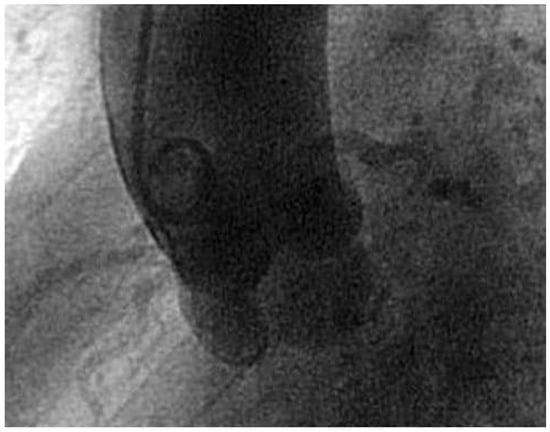

11 Jahre zuvor war bei der Patientin eine Herzkatheteruntersuchung wegen atypischer pektanginöser Beschwerden durchgeführt worden. Die Koronarien waren unauffällig gewesen. Bei nochmaliger Durchsicht der Aortographie zeigten sich die vier Taschen der QAK (Figure 4).

Figure 4. Die Aortographie zeigt die vier fast symmetrischen Taschen.